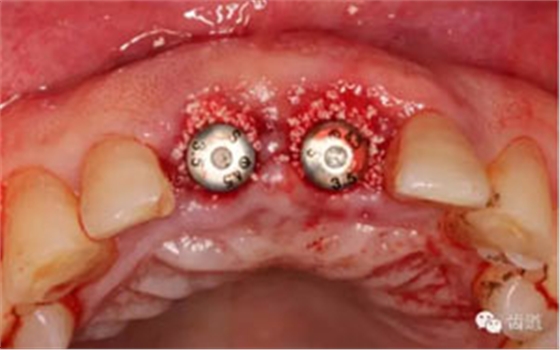

小直徑愈合基臺(tái)就位后唇側(cè)植骨

更換大直徑愈合基臺(tái)